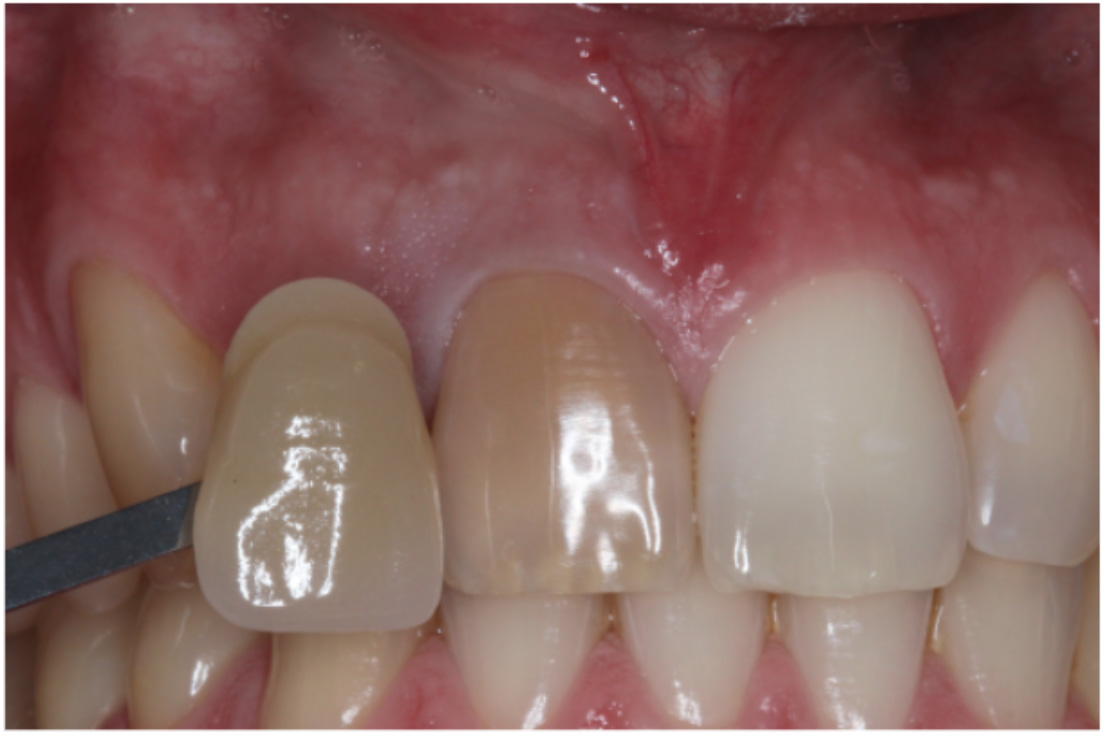

Definitive restoration

- Rubber dam

- Clean the access cavity using ultrasonics and hypochlorite

- Composite restoration. I would recommend placing a light shade of composite (B1) (Figure 10)

- Remind the patient that the shade can relapse over time and the bleaching may need topping up externally periodically.